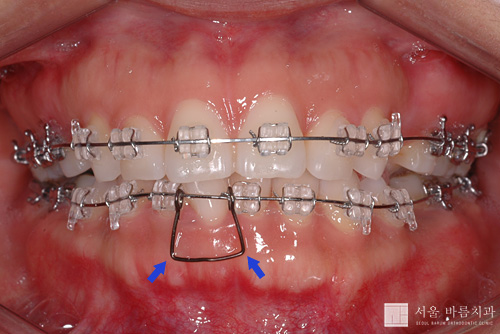

이번 달에는 하악의 와이어를 보다 굵은 것(0.018inch Ni-Ti wire)으로 교체하면서, #41 치아 좌우로 공간을 벌리기 위해서 스프링을 넣었습니다.

스프링의 종류에는 여러가지가 있지만 지금 사용한 것은 temple spring이라고 하는 것입니다. 위의 사진에서 보시는 것과 같이 생겼습니다. 모양은 다소 안좋지만, 조작하기 편리하고 역학적으로 치아를 이동시키기에 상당히 이상적인 특성을 지니고 있는 스프링입니다.

위의 파란 화살표 부위가 벌어지면서 좌우의 치아를 옆으로 밀어내는 작용을 합니다.